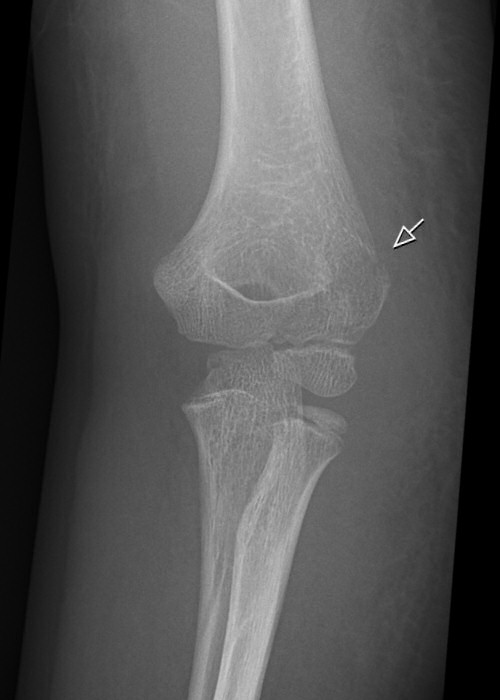

Normal sidobild (vuxet skelett)

Fettkuddar anteriort och posteriort om distala humerus, antyder fraktur (vuxet skelett)